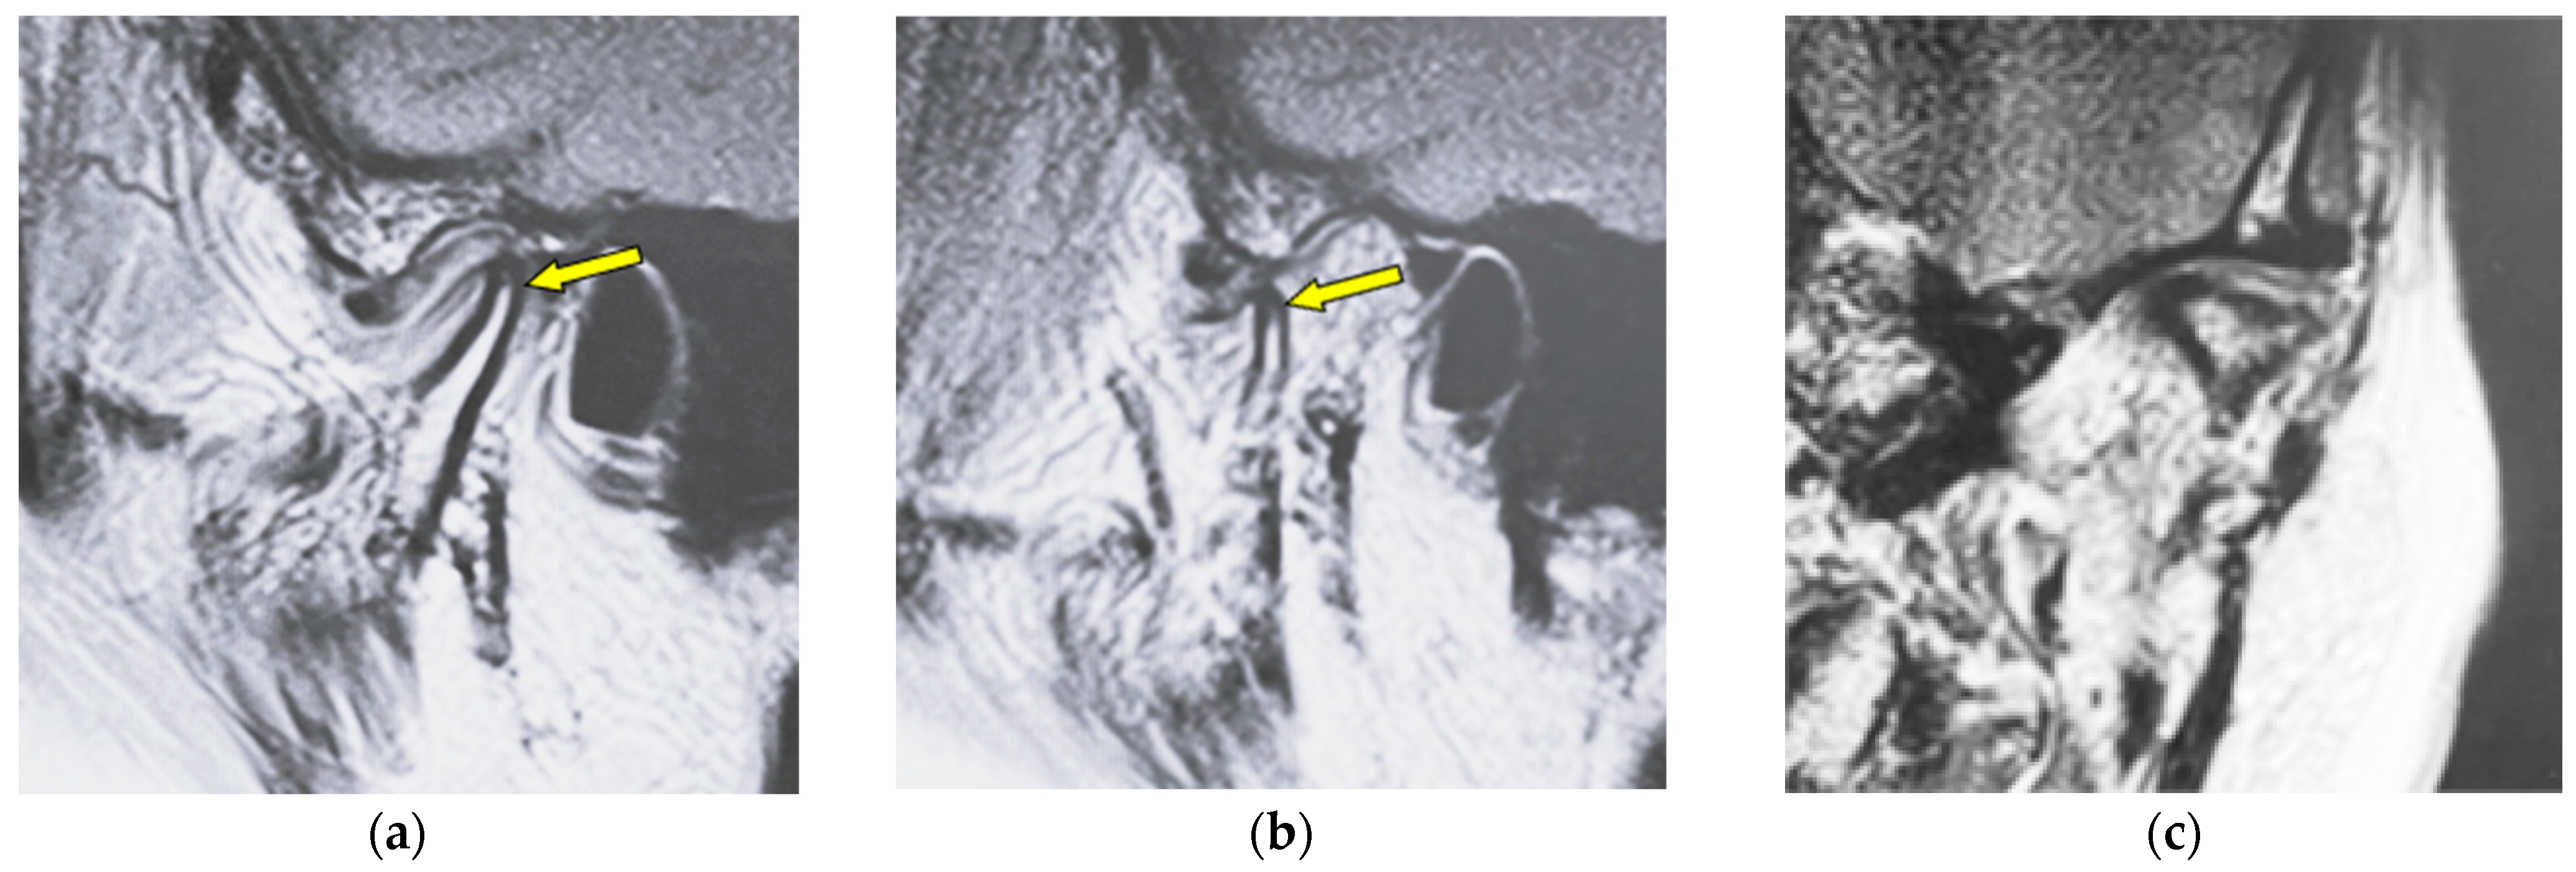

| Erosion | Local area of rarefaction in compact bone with a lack of cortical bone continuously |

| Flattening | Loss of convexity of the condylar head outline and keeping the cortical bone continuously |

| Osteophyte | Local forward outgrowth of the condyle bone with an acute angle from the top of the head of the mandible |

| Atrophy | Reduction in anteroposterior widths in the mandibular condyle without a round form |